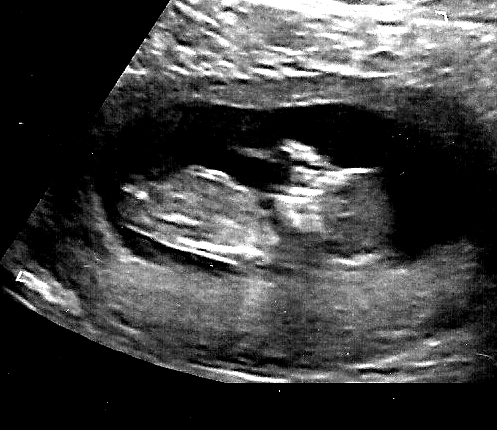

12weeks 5 days

Attachment 27038

Any idea is this a boy or girl? Thank you very much in advance :)